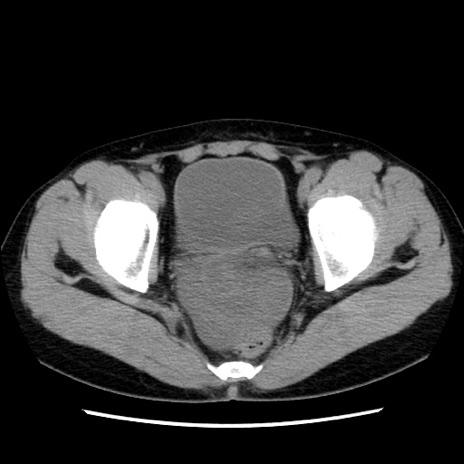

症例10(横断像)

【症例】 50歳代女性

【主訴】 腹痛

【現病歴】前日生レバーを食べた。今朝に排便あり。 昼前に突然発症の腹痛を生じ、当院救急外来を受診した。

【既往歴】 子宮筋腫にてで子宮全摘後

【身体所見】 意識清明、腹部:平坦、軟、下腹部やや左を中心に圧痛・反跳痛あり、筋性防御あり

【データ】WBC 7800、CRP 0.07